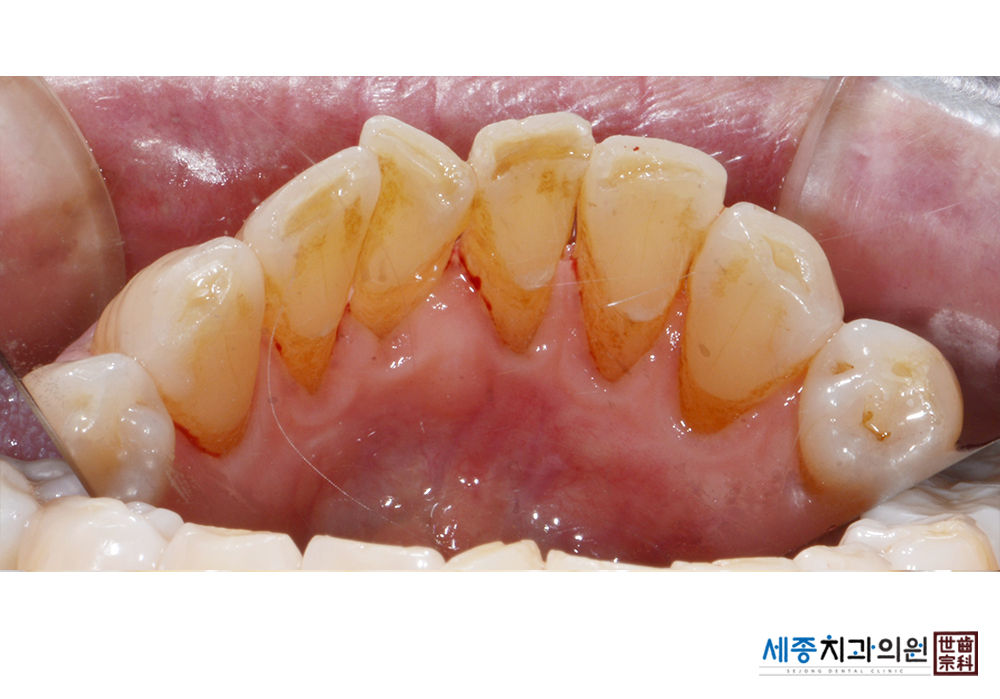

[스케일링] 치주질환 예방 스케일링

치료후 : 2021-01-06

가글마취&저주파 스켈러를 사용한 스케일링